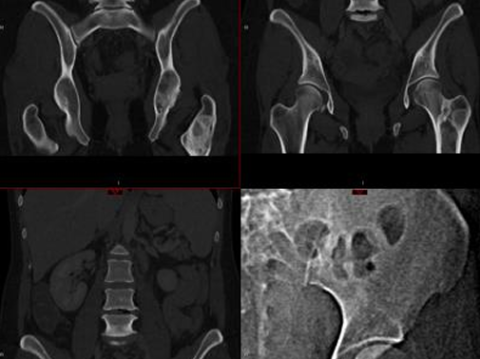

ECR2026 fig1.png

Polyostotic Fibrous Dysplasia of the left iliac bone and femur demonstrates a ground-glass appearance and cystic features, surrounded by thick sclerotic rims.